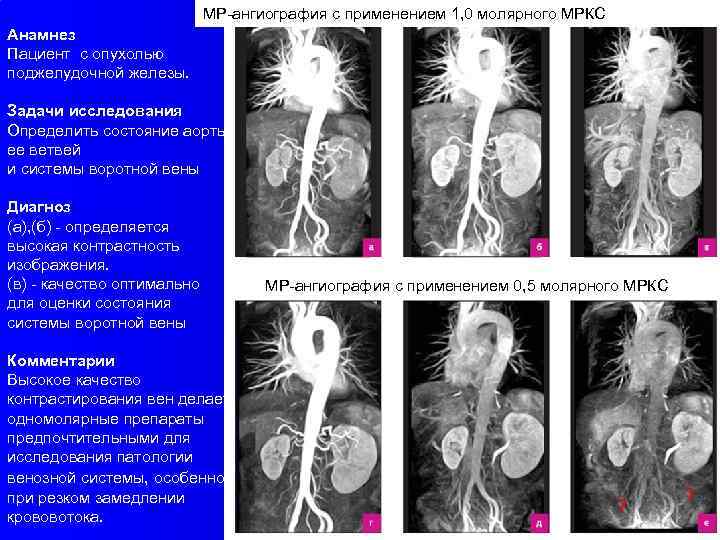

МР-ангиография с применением 1, 0 молярного МРКС Анамнез Пациент с опухолью поджелудочной железы. Задачи исследования Определить состояние аорты, ее ветвей и системы воротной вены Диагноз (а), (б) - определяется высокая контрастность изображения. (в) - качество оптимально для оценки состояния системы воротной вены Комментарии Высокое качество контрастирования вен делает одномолярные препараты предпочтительными для исследования патологии венозной системы, особенно при резком замедлении крововотока. МР-ангиография с применением 0, 5 молярного МРКС ? ?